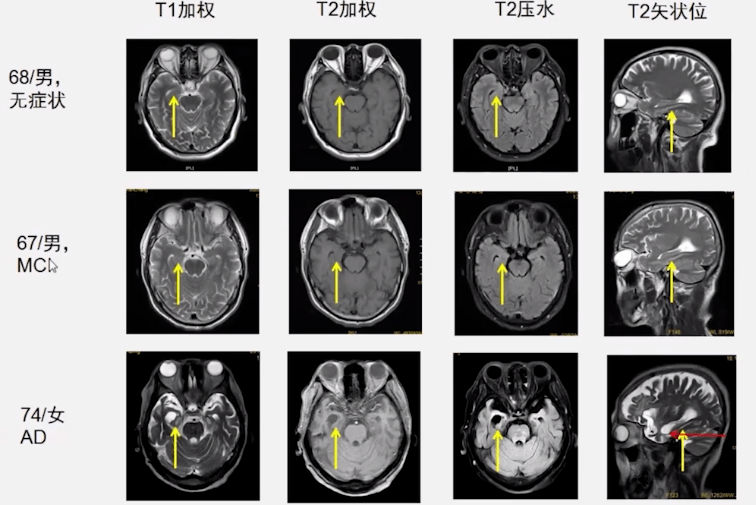

老年性脑萎缩的影像学比较总结2.